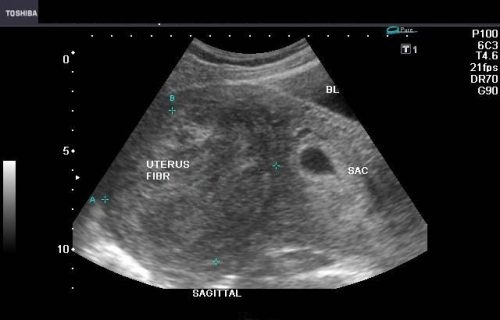

U xơ tử cung và túi thai